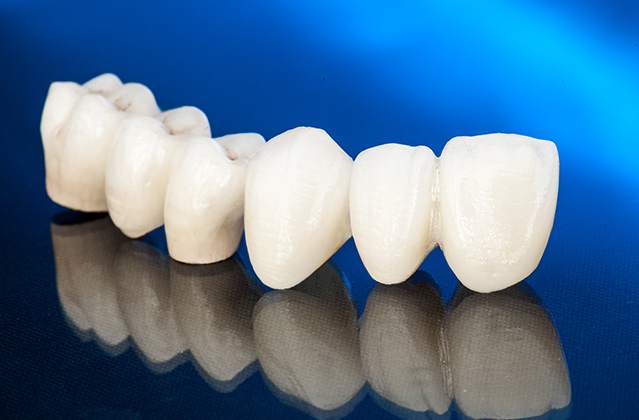

Cerec Porcelain Restoration

Sophisticated CAD/CAM system for the production of all-ceramic inlays, onlays, partial crowns, veneers and full crowns for anterior and posterior teeth.